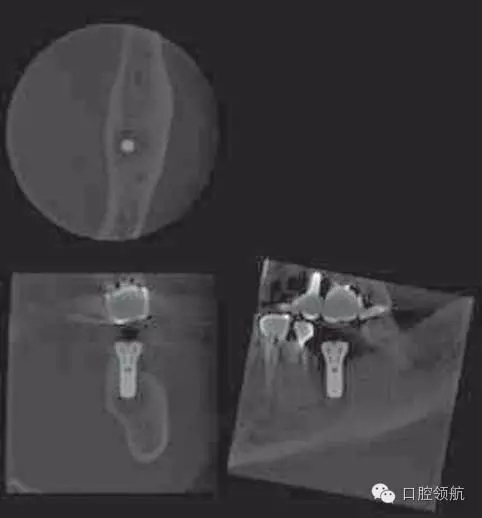

術后第18天,進行CBCT的確認(圖5),種植體周圍發(fā)現(xiàn)不透過影像,而且種植體有松動,因此在浸潤麻醉下拔除(圖6~圖8)。

圖5 術后18天CBCT的影像。